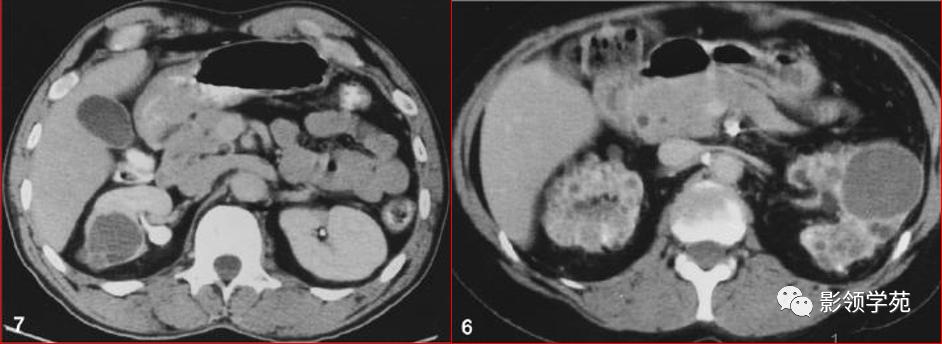

Ⅲ级为较多合并症的囊性病变

较多厚壁分隔

囊壁厚

明显且不规则钙化

多房性病变,包括多房囊性肾瘤

部分为良性,部分为恶性,提倡手术探查或切除.CT诊断良恶性存在困难,影像学表现良性特征较多时,则主张肾脏部分切除

Bosniak Ⅲ级

Ⅳ级为囊性癌,具有明显恶性特征

密度不均

有明显实性成分,如壁结节

强化成分(良性病变亦可强化,但程度较轻)

提倡手术切除,标准肾癌根治术